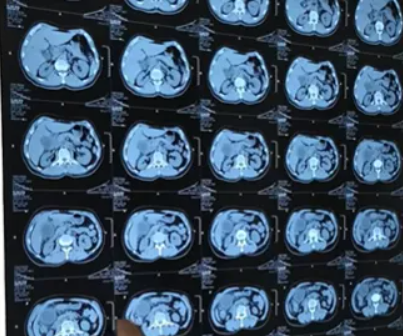

我院双镜联合微创术

功能保留:双镜配合,取石彻底,保留胆囊功能微创快速:腹部仅几厘米小孔,出血少、疼痛轻安全低复发:操作精准,并发症少、复发率低适用广:单发、多发结石均可考虑(需胆囊功能良好)